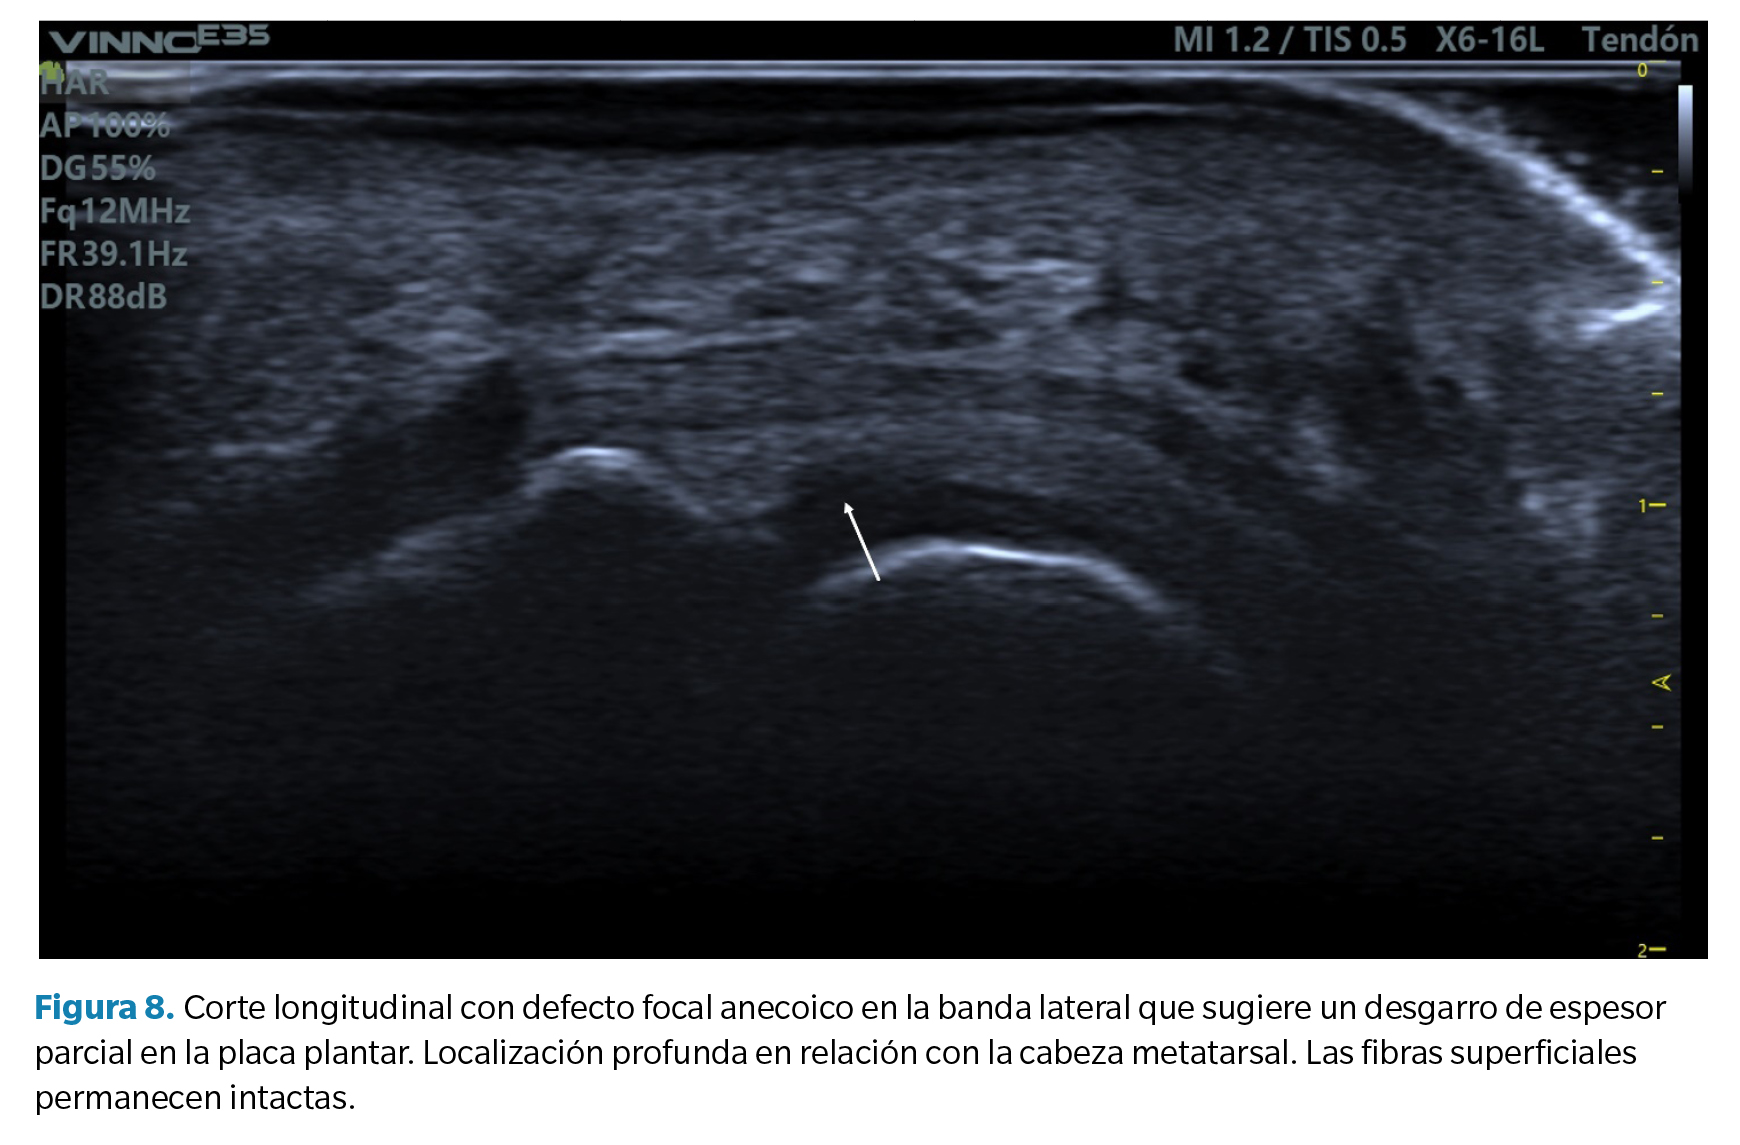

- Defecto focal anecoico o hipoecoico. Se aprecian como una hendidura discreta en la zona profunda del tejido (zona que articula con la cabeza metatarsal) en su margen lateral. Cuando las fibras superficiales están intactas hablamos de un desgarro de espesor parcial, mientras que cuando dicho desgarro atraviesa todo el tejido hasta su región superficial hablamos de un desgarro de espesor total39 (Figura 8).

Los argumentos a favor del predominio de fuerzas compresivas se basan en que el factor etiológico más claramente establecido en la literatura científica es la presencia de un segundo metatarsiano largo o un primer metatarsiano corto. En ambos supuestos, el exceso de protusión metatarsal o la insuficiencia del primer radio aumentan las fuerzas compresivas sobre la cabeza del segundo metatarsiano. Esto a su vez se corresponde con un patrón habitual de lesión que observamos en ecografía: lesiones focales en la porción central profunda (midsubstance) de la placa en su margen lateral, donde el cóndilo metatarsal comprime con mayor fuerza.